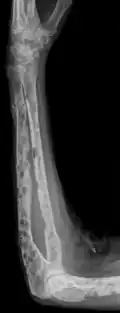

The diagnostic examination of a person with suspected multiple myeloma typically includes a skeletal survey. This is a series of X-rays of the skull, axial skeleton, and proximal long bones. Myeloma activity sometimes appears as "lytic lesions" (with local disappearance of normal bone due to resorption) or as "punched-out lesions" on the skull X-ray ("raindrop skull"). Lesions may also be sclerotic, which is seen as radiodense.[76] Overall, the radiodensity of myeloma is between −30 and 120 Hounsfield units (HU).[77] Magnetic resonance imaging is more sensitive than simple X-rays in the detection of lytic lesions. An MRI may supersede a skeletal survey, especially when vertebral disease is suspected. Occasionally, a CT scan is performed to measure the size of soft-tissue plasmacytomas. Nuclear Medicine Bone scans are typically not of any additional value in the workup of people with myeloma (no new bone formation; lytic lesions not well visualized on nuclear bone scan).

X-ray of the forearm, with lytic lesions -

Multiple myeloma in the upper arm -